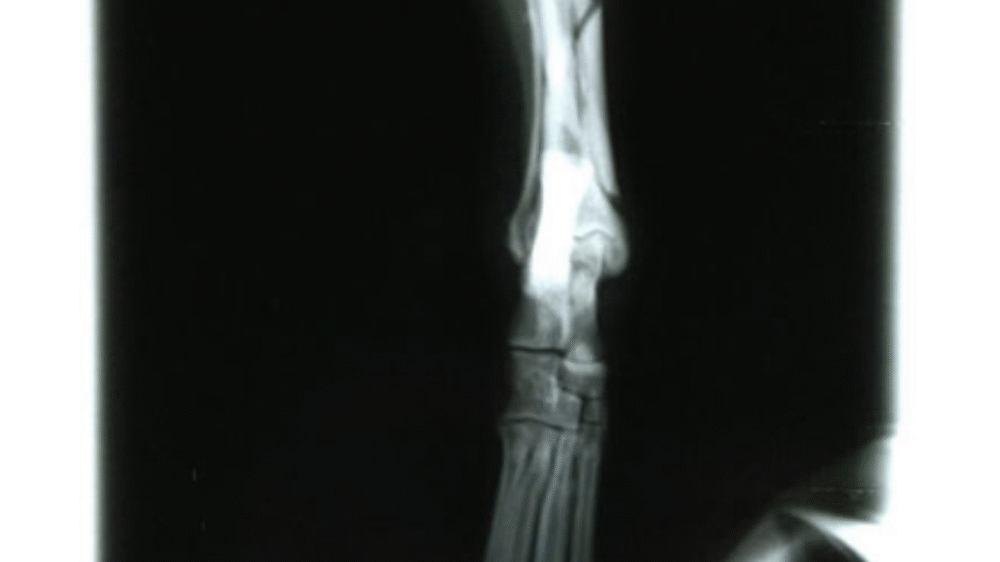

Radius and Ulna Fracture Repair

Example of Minimally Invasive Radius and Ulna Fracture Repair.